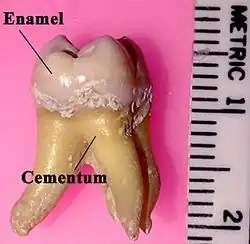

Forma-se apicalmente à margem gengival, e não é normalmente visível. Pode ser detectado pela exploração tátil com a sonda periodontal ou um explorador fino, e é normalmente evidente por sua superfície áspera. Se a margem gengival for retraída por um jato de ar ou por algum instrumento dental, o cálculo subgengival pode ser evidente e precisamente apical à junção esmalte-cemento.

O cálculo supragengival consiste de 70% a 90% de sais inorgânicos, principalmente na forma de fosfato de cálcio(Ca3[PO4]2). O cálculo também contém quantidades variadas de carbonato de cálcio e fosfato de magnésio. A porção inorgânica é quimicamente similar à porção inorgânica do osso, dentina e cemento. Os componentes orgânicos do cálculo envolvem proteína e complexos de polissacarídeos derivados da placa dental, células epiteliais descamadas e glóbulos brancos.